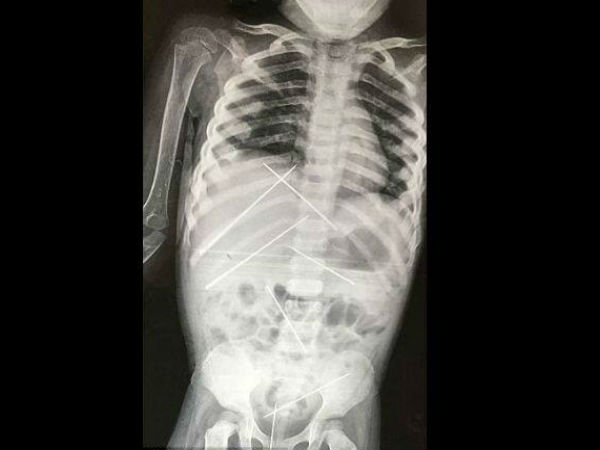

பில்லி, சூனியம் வைக்க பெண் குழந்தை உடலில் ஊசிகளை புகுத்திய கொடூரன்!

ஓரிரு வாரங்களுக்கு முன்னர் கொல்கத்தாவின் ஒரு மருத்துவமனையில் உள்ளுறுப்புகளில் பல காயங்களுடன் 3 வயது குழந்தை அனுமதிக்கப்பட்டது. அந்த குழந்தையின் உடலில் பெரியளவிலான ஊசிகள் குத்தப்பட்டிருந்தன.

ஆனால், சோதனையின் போது குழந்தையின் உடலில் நான்கு அங்குல அளவிலான ஏழு ஊசிகள் சொருகப்பட்திருந்ததை அறிந்தனர். கல்லீரல் மற்றும் சிறுநீர் பையில் இரண்டு ஊசிகள், சிறுநீரகம், பெண்ணுறுப்பு, வயிற்றின் அடிபகுதியில் ஒவ்வொரு ஊசிகள் இருந்ததை பரிசோதனையில் கண்டறிந்தனர்.

அந்த ஊசிகளை மருத்துவர்களால் அகற்ற முடியவில்லை. அகற்றுவதன் காரணமாக மேலும், இன்பெக்ஷன் அல்லது பிரச்சனை அதிகரிக்குமோ என அஞ்சினர்.

மூன்று நாட்கள் போராட்டத்திற்கு பிறகு அந்த ஊசிகளை மருத்துவர்கள் அகற்றினர். பிறகு இன்பெக்ஷன் பரவாமல் தடுக்க மருந்துகள் கொடுத்து பரிசோதனை செய்து வந்தனர்.

ஆனால், பரிதாபத்திற்குரிய குழந்தை, நோய் தொற்றை எதிர்கொள்ள முடியாமல் மடிந்து போனது. அந்த ஊசிகளின் காரணத்தால் உடல் முழுவதும் இன்பெக்ஷன் பரவியதன் காரணமாக அந்த குழந்தை இறந்ததாக காரணம் கூறப்பட்டது.